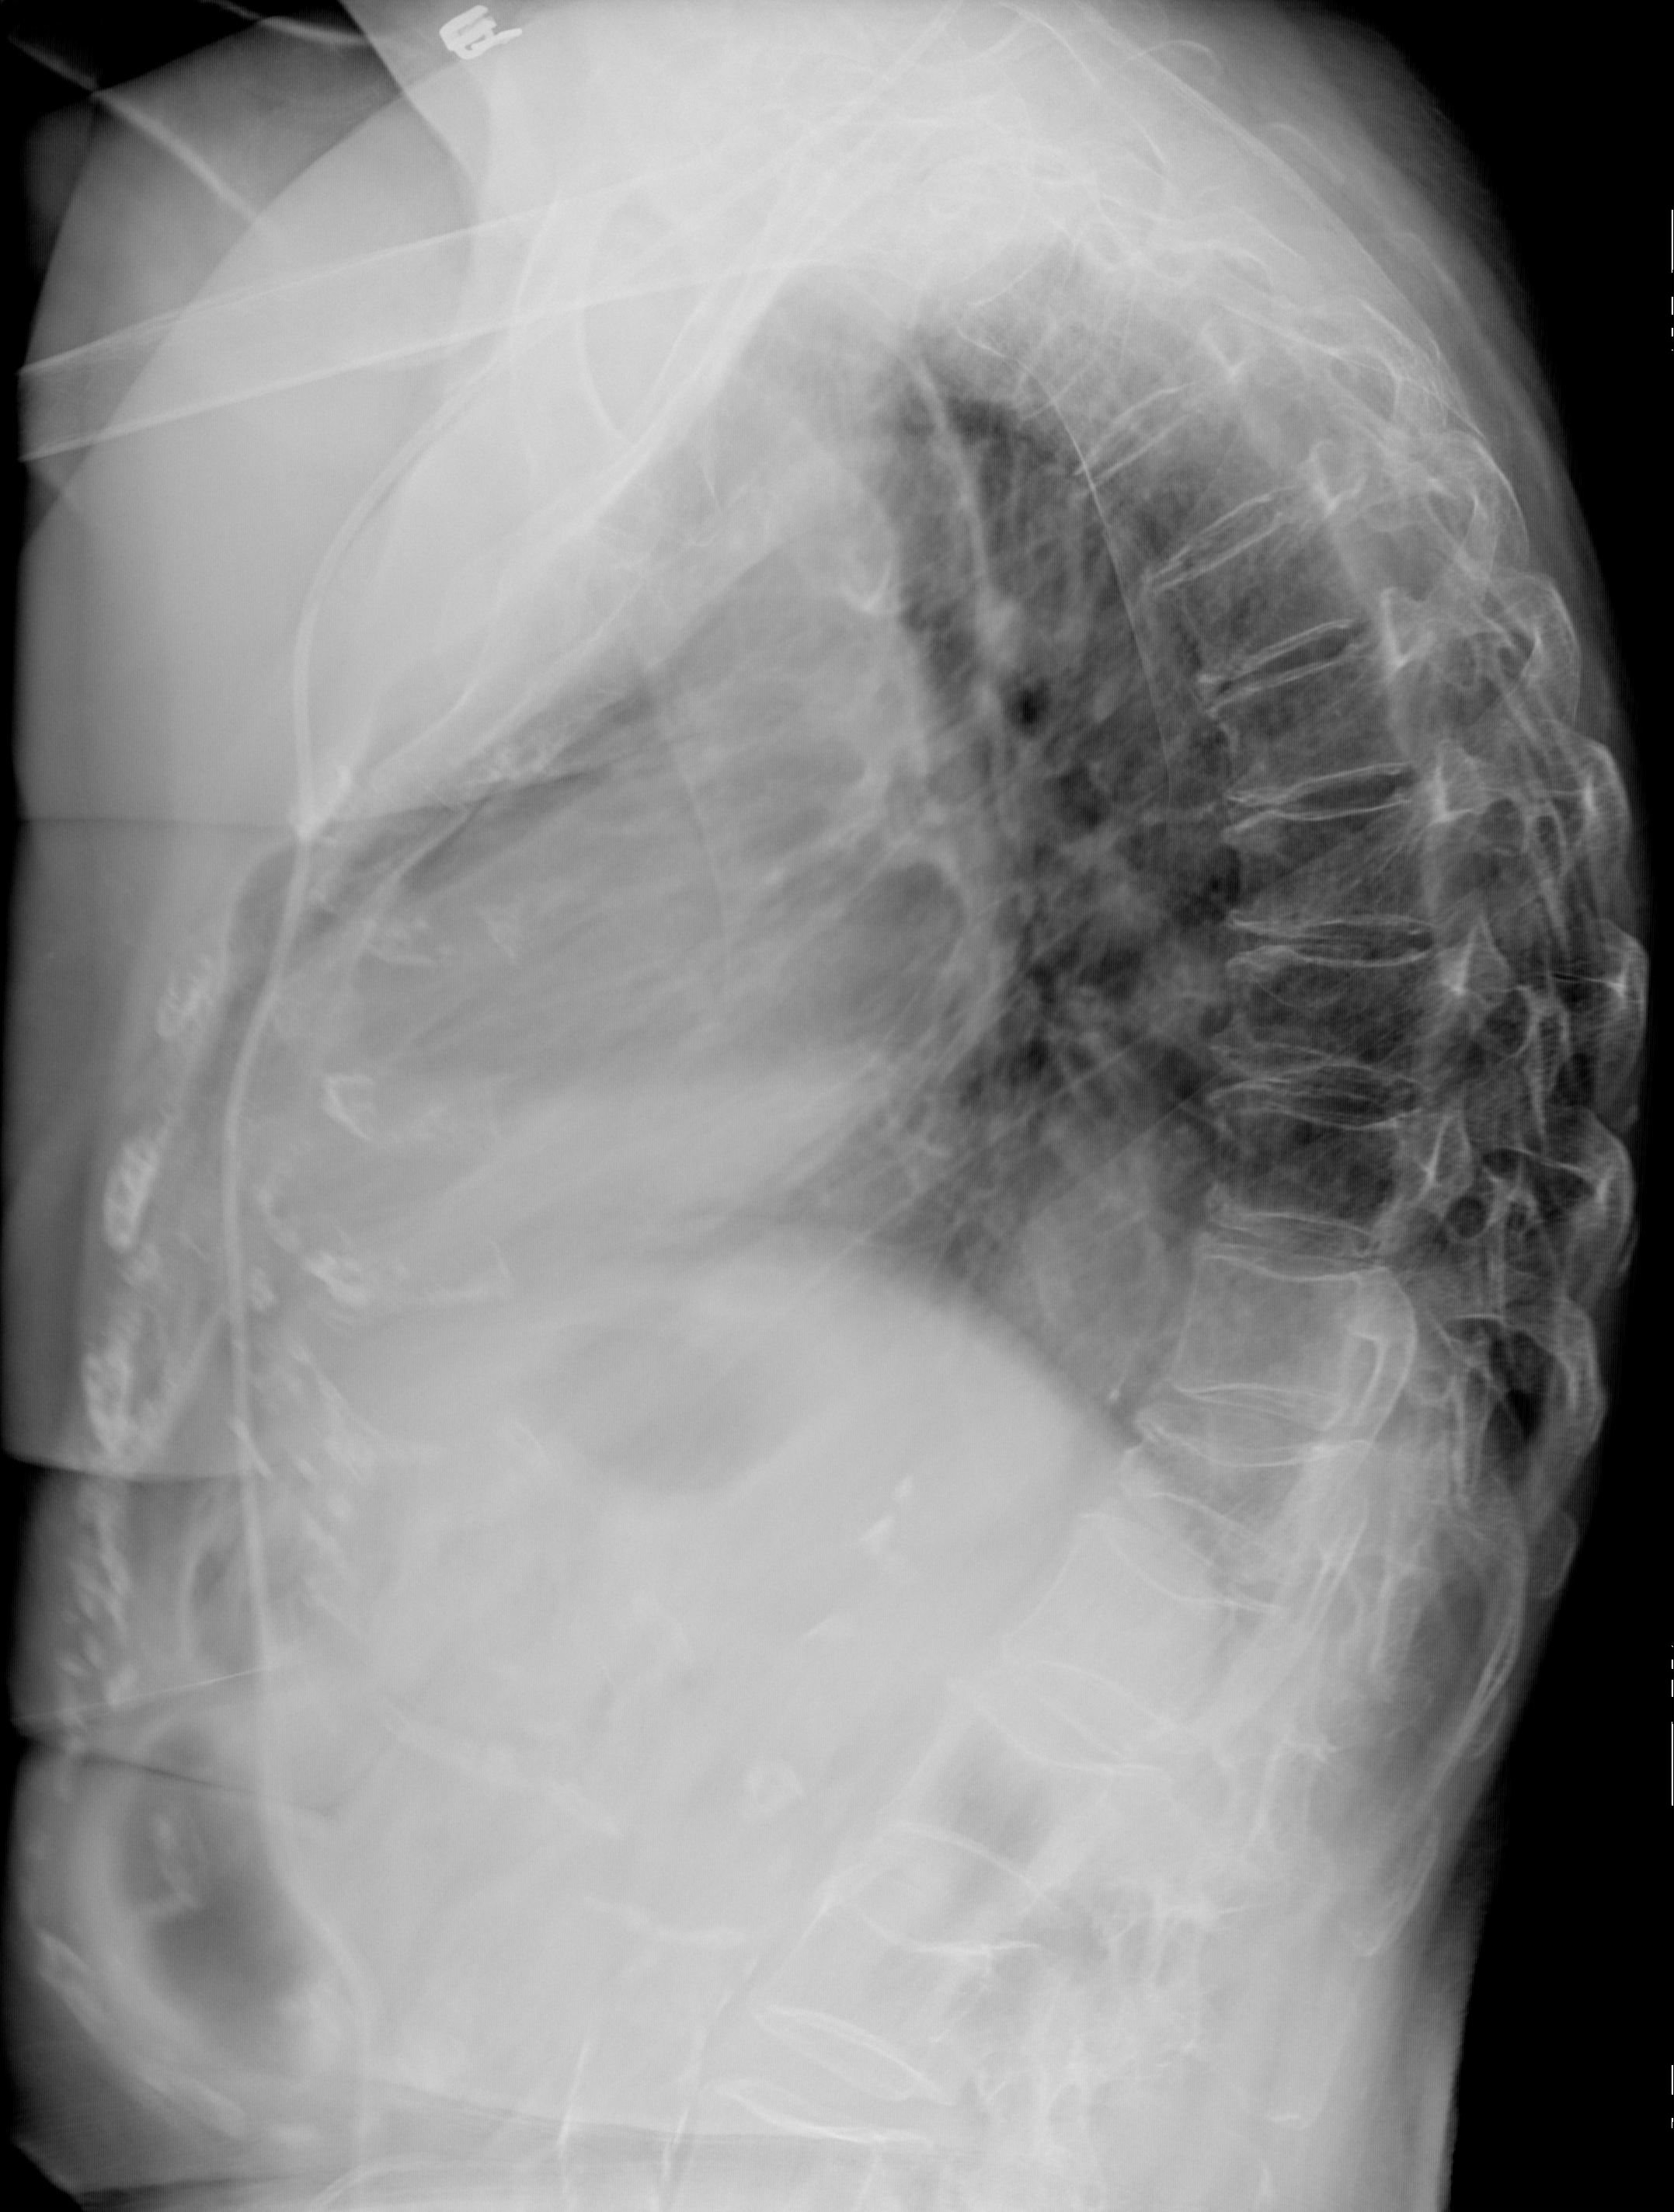

Рентген на дому: по вашему адресу приезжает врач-рентгенолог, травматолог-ортопед с мобильным рентгеновским аппаратом, проводит диагностику травмы или заболевания, делает необходимые рентгенограммы, дает рекомендации по дальнейшему лечению. Получить качественные снимки в домашних условиях возможно благодаря уникальной методике, разработанной МосРентген Центром для института  Склифосовского